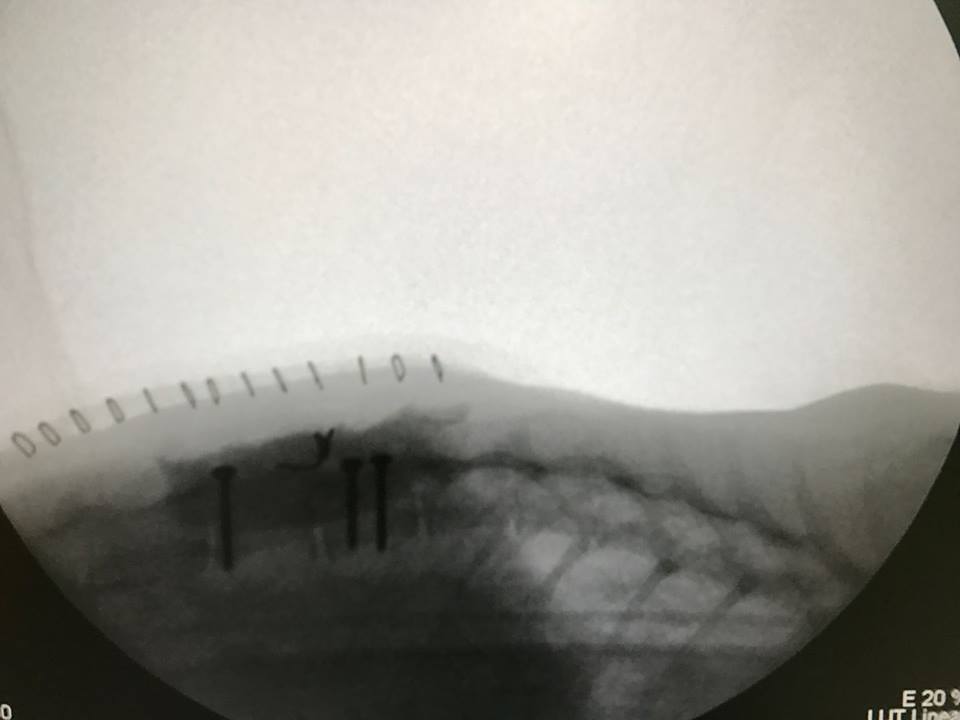

主題: 東湖市場TNR浪貓受傷後腳拖行脊椎骨折錯位 申請者姓名: lois tsai 花色: 申請日期: 2017-03-07 22:42:26 申請者部落格: 申請者臉書網址: 所在縣市/合作醫院: 台北市/其他院所醫助專案(醫院請先MAIL溝通) 治療費用: 45365元 需求人數: 48人 已結案 (2024-06-01 13:33:51) 報名人員: 蹦蹦(已付款)、Shane(已付款)、Amber Chung(已付款)、艾利狐(已付款)、yenshi(已付款)、羅曉筑(已付款)、葉宸瑜(已付款)、Bella Chung(已付款)、基隆丫貴 x2(已付款)、高點點 x2(已付款)、以四面佛名義ㄐㄩㄢㄗㄥ(已付款)、Diamond(已付款)、Ying-Jui Syu x2(已付款)、Michelle Kuan(已付款)、陳昱先(已付款)、可樂 x5(已付款)、Li Chen(已付款)、羅文君、小娜 x2(已付款)、Leo Liao(已付款)、Abby Lin(已付款)、Adeline Chen(已付款)、Joe Hook x3(已付款)、QQ(已付款)、yjline(已付款)、簡慧嬿 x2(已付款)、Judy(已付款)、以四面佛名義(已付款)、Peiyu(已付款)、小屁(已付款)、Alisa Huang(已付款)、陳冠綸(已付款)、snoopypeggy(已付款)、hsinho x2(已付款)、saya6084(已付款)、思~(已付款)、戀糖bear(已付款)、 候補人員: 動物病情說明: 東湖市場已TNR兩年的貓咪小恢

在還沒通報醫助前我先帶她到角落動物醫院照X光及血檢確定是脊椎骨折錯位

二月底在台大神經科吳醫師進行手術後已轉往承諾動物醫院後續治療及復健動物近況說明: 小恢在角落動物醫院醫療X光住院費用約12000已自付. 小恢在台大手術的費用須申請醫助, 之後已轉往承諾動物醫院後續治療及復健